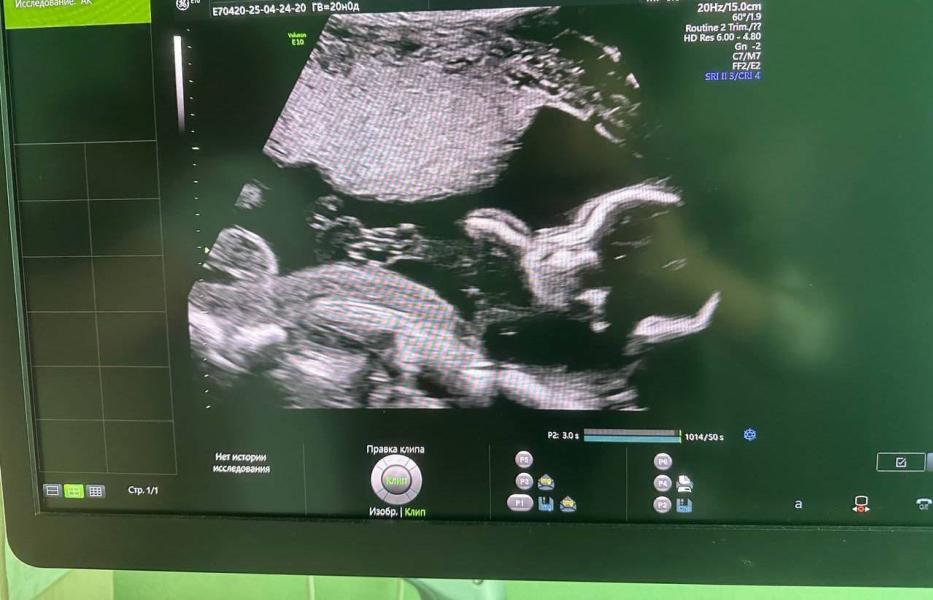

Сегодня я посетила второй скрининг.

Ранее мне ставили риски в развитии плода, но сегодня врач сообщил, что мой малыш развивается на шесть дней вперёд с, без каких-либо патологий. Воды у меня в норме.